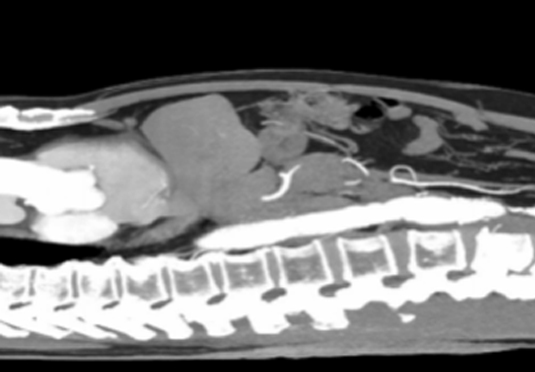

血管新生:激發(fā)周圍組織中的血管生長,過程被稱為血管新生或腫瘤血管化;血管不規(guī)則分布,缺乏正常結(jié)構(gòu)和功能,致血液供應(yīng)不足和缺氧情況。

組織破壞和浸潤:侵襲和破壞正常組織,穿過正常組織的屏障,入侵到其他組織和器官中,形成遠(yuǎn)處的轉(zhuǎn)移,顯示出惡性腫瘤細(xì)胞的擴(kuò)散能力。

微創(chuàng)射頻消融術(shù)